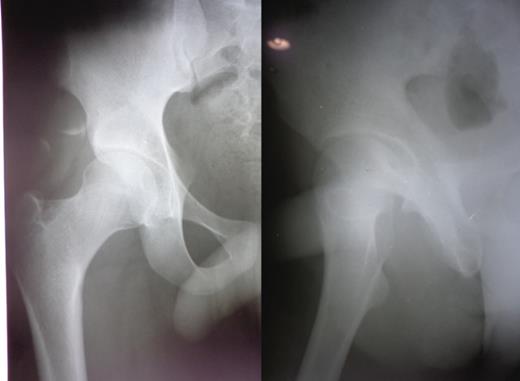

A 23-year-old male pavement dweller was brought to the emergency department of this hospital after being hit by a tempo. The patient was in a state of shock with an open right-sided anterior hip dislocation with the femoral head being visible in the inguinal region (Fig. 1). The neurovascular status of the right lower limb was intact. Immediate resuscitation was done and hip radiographs (Fig. 1) were taken, which showed an anterior-inferior dislocation with an inferior pubic ramus fracture on the left side. The patient was immediately transferred to the operating room where the wound was thoroughly debrided and the femoral head was relocated within 5 hours of sustaining the trauma (Fig. 2). The wound after surgical debridement was 8 × 6 cm in dimensions, which was primarily closed after checking for the stability of the reduction. The patient was started on intravenous metronidazole, amikacin and ceftriaxone for 5 days, followed by oral amoxicillin for a week. The patient was kept non-weight-bearing on skin traction for 6 weeks. The wound healed satisfactorily with no evidence of infection, nor any episode of re-dislocation at 6 months (Fig. 3). The patient was unfortunately lost to follow-up.